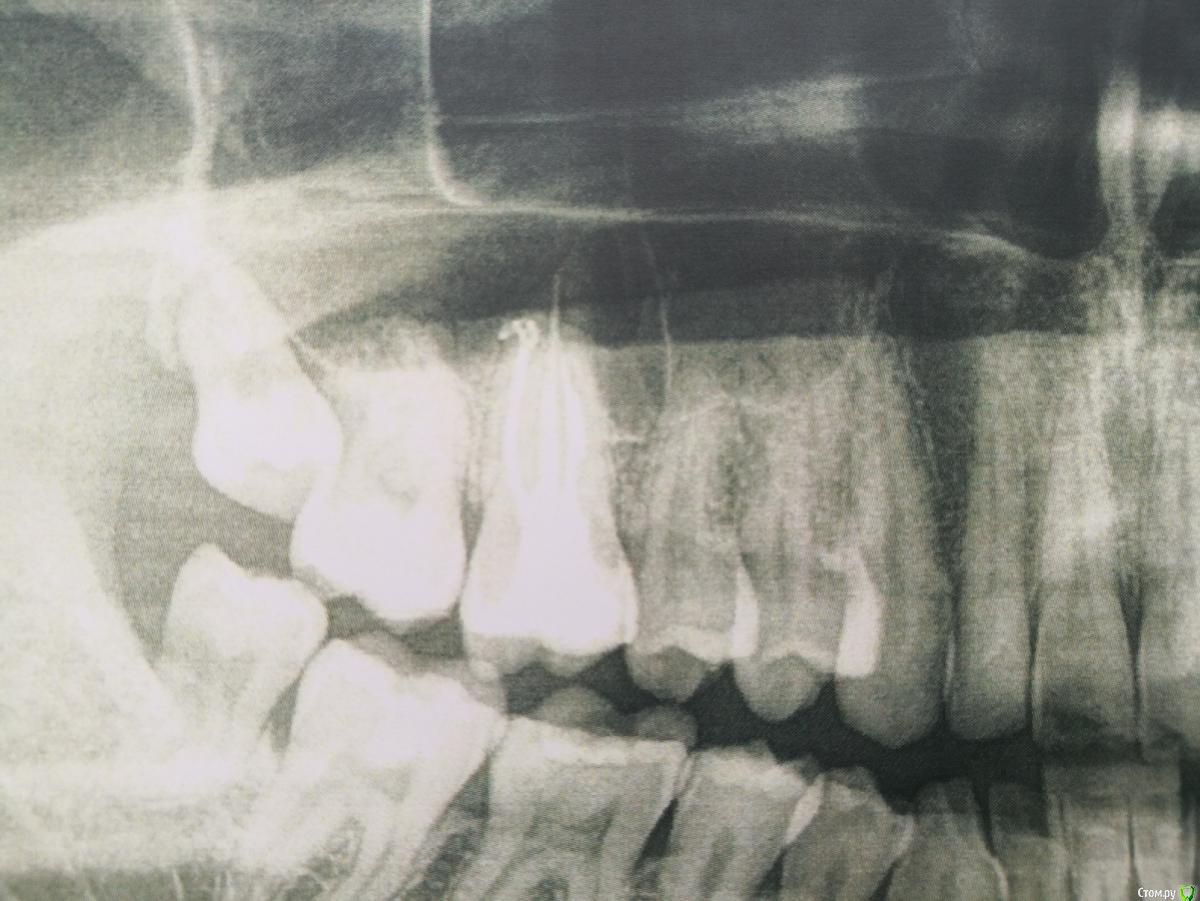

aleks.k Опубликовано 1 февраля, 2019 Автор Поделиться Опубликовано 1 февраля, 2019 Фото Ссылка на комментарий

kramer Опубликовано 1 февраля, 2019 Поделиться Опубликовано 1 февраля, 2019 Сделайте нормальный снимок. А лучше КТ. Скорее всего причина в 6. Ссылка на комментарий

aleks.k Опубликовано 3 февраля, 2019 Автор Поделиться Опубликовано 3 февраля, 2019 Добрый день! Спасибо за ответы. КТ сделаю, удивило то, что мой стоматолог приговорил зуб не задумываясь и не отправляя на КТ, сразу же записав на удаление. А что за искривленный белый отросток на верхушке 6го зуба? Ссылка на комментарий

aleks.k Опубликовано 5 февраля, 2019 Автор Поделиться Опубликовано 5 февраля, 2019 Добрый день! Сделал КТ. Посмотрите пожалуйста.Есть 2 мнения очных стоматологов, пока никто из них КТ не видел, мнение на основании предыдущего панорамного снимка:1. Надо удалять 6 зуб справа2. Который и депульпировал 6 зуб сказал, что проблемы в 6 зубе нет, зуб мудрости нужно оттянуть брекетами. Размер файла 131 мб. http://fayloobmennik.cloud/7349278 Ссылка на комментарий